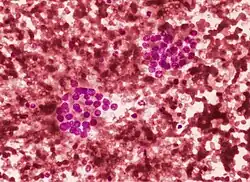

Thyroid cytopathology of Bethesda category III with clotting artifact

Thyroid cytopathology of Bethesda category III with clotting artifact Category IV

Category IV Category V with intranuclear cytoplasmic inclusion

Category V with intranuclear cytoplasmic inclusion Category V with nuclear groove (arrow)